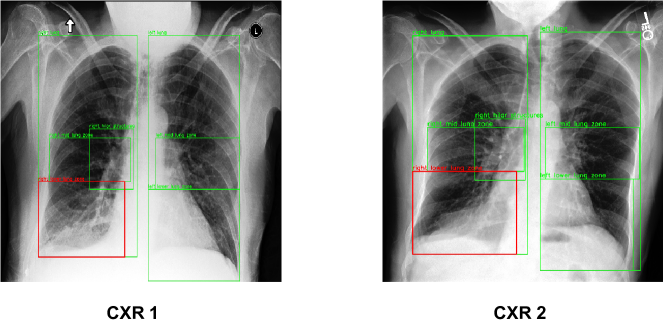

We visualize the model predictions for different pathologies. Figure 3 showcases an input image pair for the pathology label ‘Fluid Overload/ Heart Failure’ where there has been a worsening in the patient’s condition. For this particular pair, the anatomical region of interest (ROI) is ‘Cardiac Silhouette’, which is depicted with a red bounding box. Other anatomical regions that our model takes into consideration when making predictions are shown in green bounding boxes. The previous and current CXRs are named ‘CXR 1’ and ‘CXR 2’, respectively. Upon close inspection, we can see there are subtle changes within the ROI as well as in other parts of the CXR. There is increased haziness in the Left and Right Lungs, and minute changes in the Cardiac Silhouette. Similarly, Figure 4, depicts the input image pair for the pathology label ‘Pneumonia’, and the case where there has been an improvement in the patient’s condition. For this particular pair, the anatomical ROI is ‘Right Lower Lung Zone’. In addition to changes within the ROI, there are significant improvements in the regions ‘Left Mid Lung Zone’ and ‘Left Lower Lung Zone’. The Local model focuses only on the ROI, whereas the Global model focuses only on the entire image. Hence, both of these fail in making correct predictions over these images. Our CheXRelNet model builds associations between various regions and hence is able to factor in the minute changes across the entire anatomy while making predictions.

Figure 3: Qualitative results for pathology D8, class: Worsened